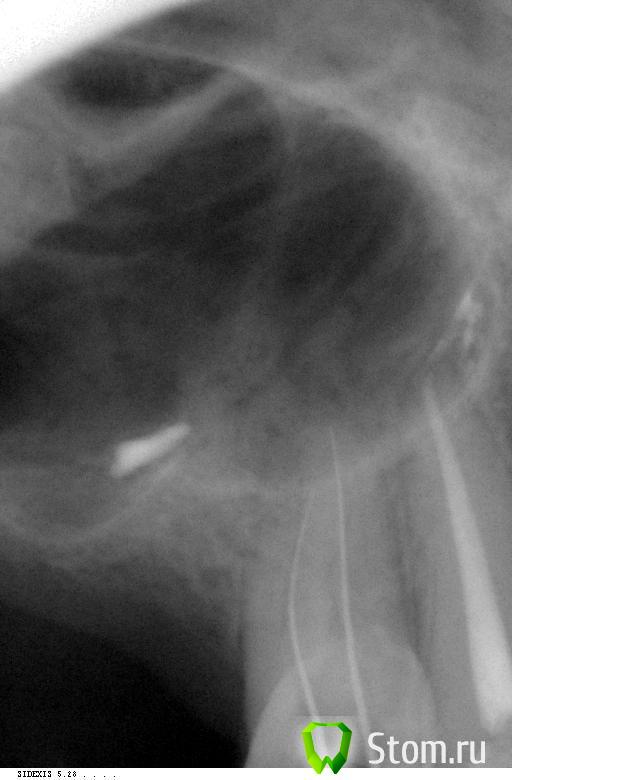

Catherine Опубликовано 5 марта, 2012 Автор Поделиться Опубликовано 5 марта, 2012 Собственно, вот снимки с иглами. Ссылка на комментарий

д-р Вит Опубликовано 5 марта, 2012 Поделиться Опубликовано 5 марта, 2012 хорошие снимки.дальше инструментами идти не стоит(имхо),помойте хлоркой разогретой с уз хорошенечко,при паковке получите картинку апекса. Ссылка на комментарий

ger_berra Опубликовано 5 марта, 2012 Поделиться Опубликовано 5 марта, 2012 хорошие снимки.дальше инструментами идти не стоит(имхо),помойте хлоркой разогретой с уз хорошенечко,при паковке получите картинку апекса.+1 Лимонку или ЭДТА добавьте при финальной ирригации. Ссылка на комментарий